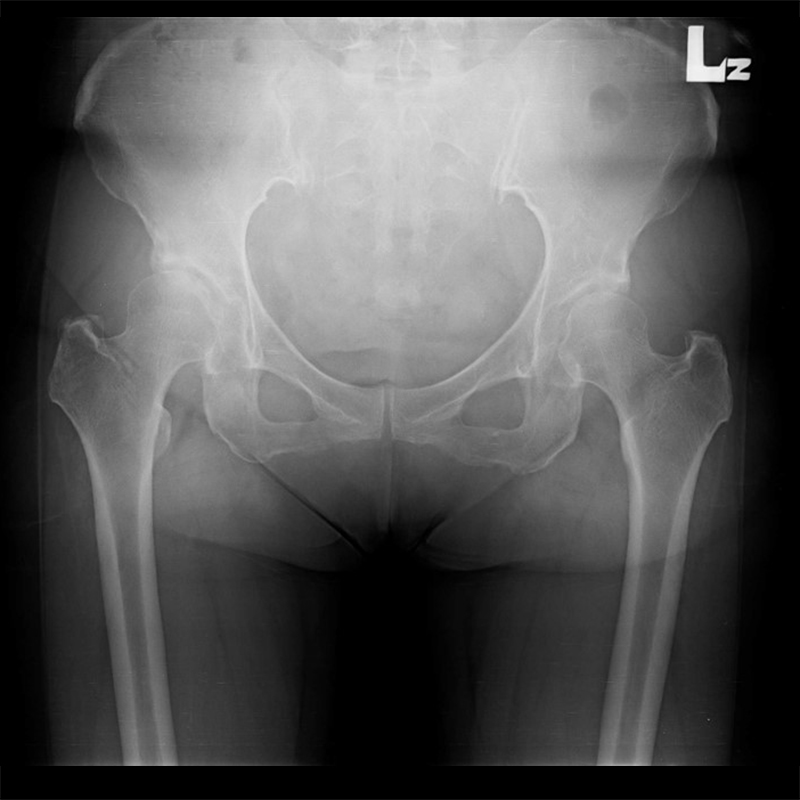

機器手臂手術 首頁 案例分享 髖關節手術 機器手臂手術 72歲 楊女士 退化性關節炎 術前 術後 60歲 彭先生骨股頭壞死 術前 術後 53歲 王女士退化性關節炎(DDH先天發育不全 CROWE TYPE 2) 術前 術後 83歲林女士退化性關節炎 術前 術後 83歲林女士退化性關節炎 術前 術後 楊女士 70歲 術前 術後 蔡女士 60歲 術前 術後